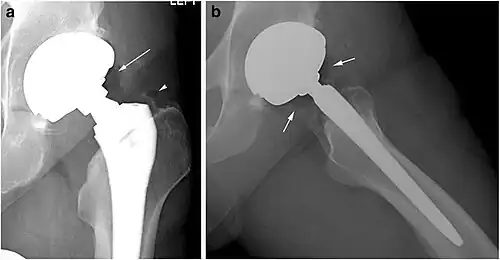

Pneumarthrosis is the presence of air in a joint. Its presentation on radiography is a radiolucent cleft often called a vacuum phenomenon, or vacuum sign.[7] Pneumarthrosis is associated with osteoarthritis and spondylosis.[8]

Pneumarthrosis is a common normal finding in shoulders[7] as well as in sternoclavicular joints.[9] It is believed to be a cause of the sounds of joint cracking.[8] It is also a common normal post-operative finding at least after spinal surgery.[10] Pneumarthrosis is extremely rare in conjunction with fluid or pus in a joint, and its presence can therefore practically exclude infection.[8]

X-ray of a hip with hip replacement and pneumarthrosis, in this case aseptic. -

A vacuum sign, or vacuum phenomenon, is a normal finding on shoulder X-rays.